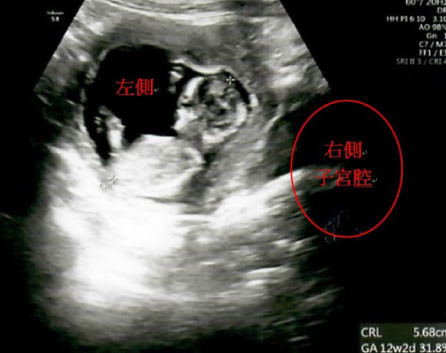

因著求子心切,加上政府推出擴大試管補助方案,讓陳小姐和先生決定直接採用試管療程,不想再浪費時間嘗試自然受孕,希望能儘快抱到孩子。於是,李茂盛院長幫王小姐進行1次取卵手術共取出9顆卵子,在受精後得到3顆囊胚,經過第4代試管的「電腦AI人工智慧系統」、「胚胎影像即時監控系統(T/L)」技術(註1),從中找出發育最好的1顆第5天囊胚,植入右側的子宮腔內,囊胚即順利著床發育,直到孕期34週又2天時,陳小姐自然產下重達2460公克的健康男寶。

▲胚胎植入右側子宮腔的位置

▲胎兒在產婦右側子宮腔內著床發育